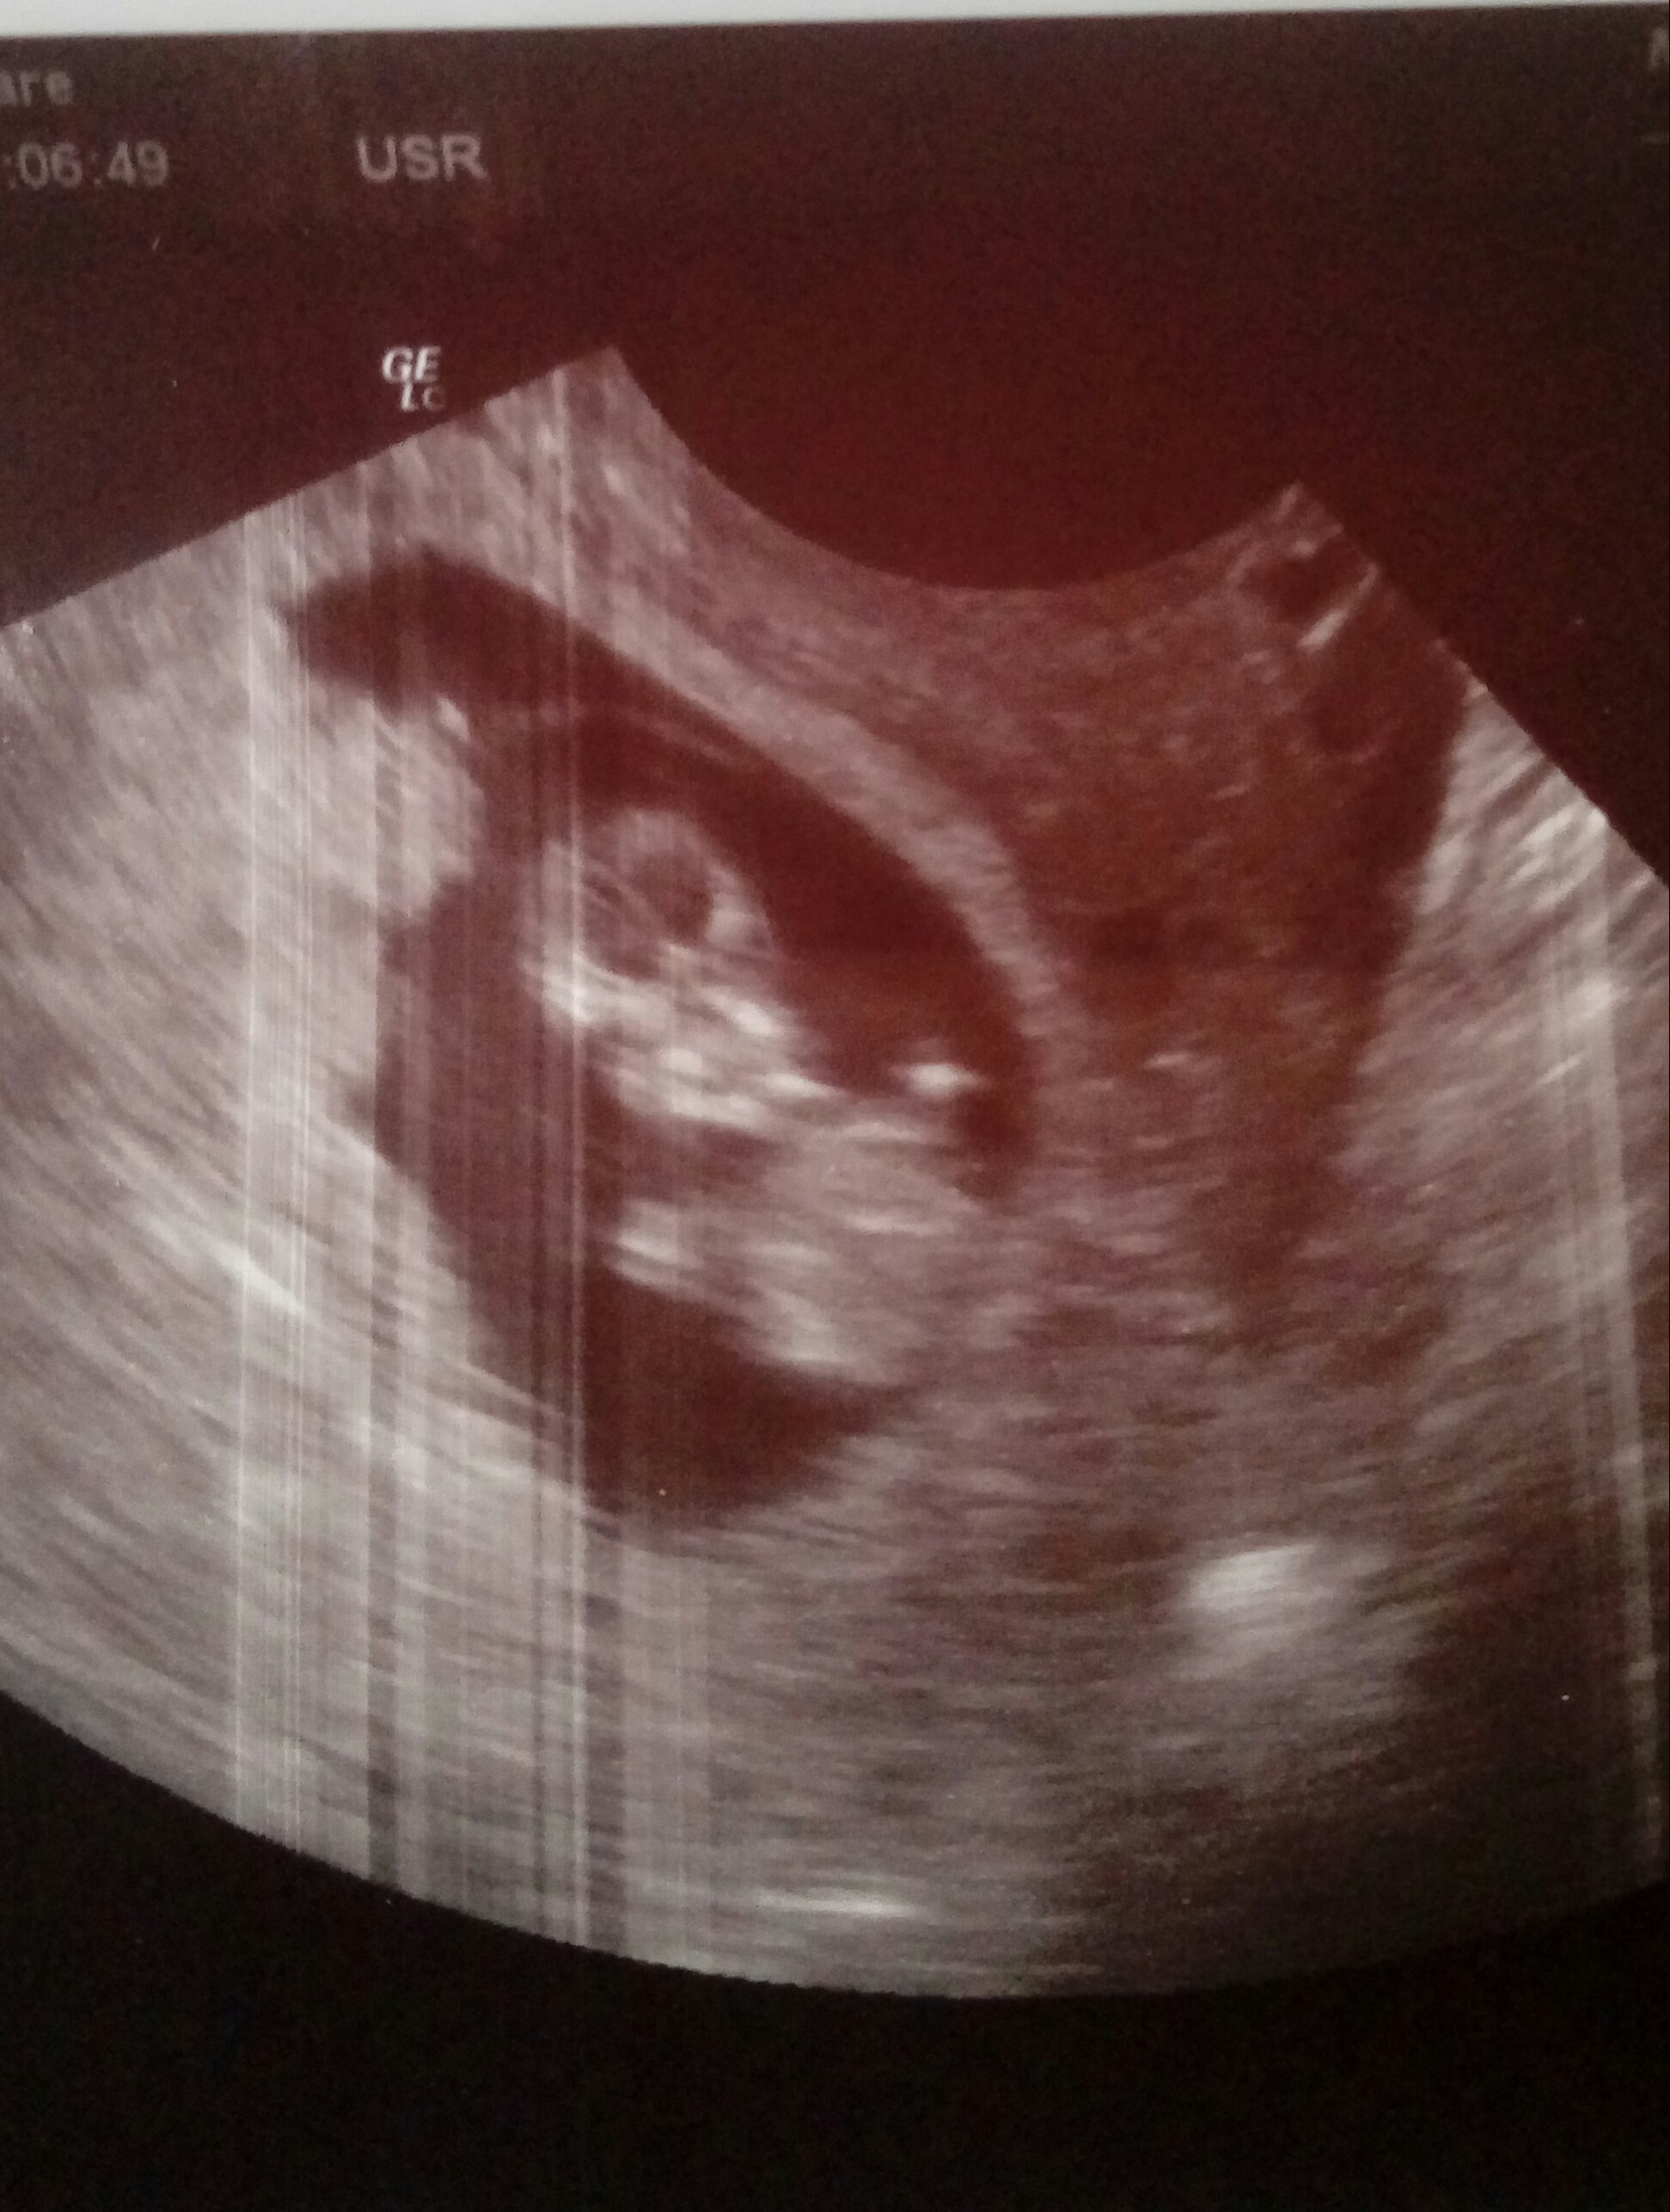

Hej dziewczyny, moj dzidziol :)

Ładnie rosnie i jak narazie wszystko jest dobrze <3

IMG_20180511_163626.jpg

• IMG_20180511_163626.jpg

53,3 KB · Wyświetleń: 542